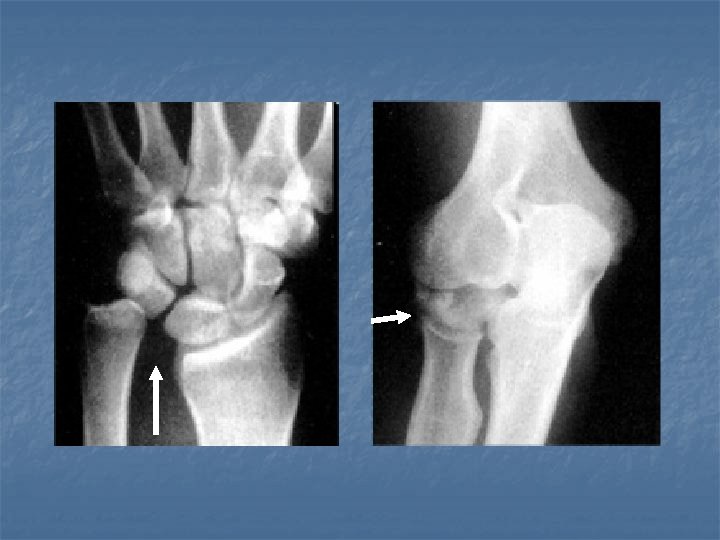

Barton Fracture n n Fracture of dorsal margin of the distal radius extending into the radiocarpal articulation. Reverse (or volar) Barton fracture: when it involves the volar aspect of distal radius

Barton Fracture

Reverse Barton